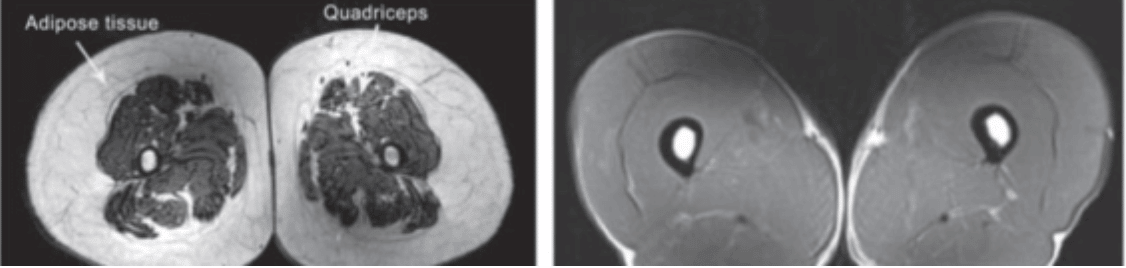

Below is a cross-section of muscle tissue in the thigh from 3 different individuals. Above is the leg of a 24 year old. This young individual is healthy at around 13% body fat. The white center circle is the femur bone surrounded by dense muscle tissue of the quads and hamstrings with a little bit of subcutaneous fat in white on the outside.

Next up for comparison, on the left is a 74 year old sedentary individual (like George). The muscles are atrophied, the bone is thinning and fat tissue has filled in both around the muscle and between it. This is the typical “aging” that we think of. But in reality, this deconditioning has taken place over the course of 30+ years.

We know that when we compare it to the final picture on the right. This is somebody the exact same age who has been highly active. In this case it is a 74 year old triathloner. And the leg looks just as fit (if not better) than that of the 24 year old.